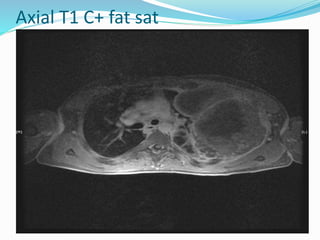

Axial T1 C+ fat sat

 So the findings are

 A large soft tissue mass arising from the upper left

chest wall.

 Detruction of much of the 4th rib is noted with tumour

extending into serratus anterior but not clearly into

subscapularis. Enlarged vessels are visible

anterolaterally. On both CT and post contrast fat

saturated MRI, the mass heterogenously enhances.

 Features are consistent with subsequent proven ewing

sarcoma of the chest wall.

 MRI

 Typically these masses are heterogeneous on MRI

as well as CT on account of numerous areas of

necrosis, degenerative cystic change and

haemorrhage . Smaller tumours are more likely be

homogeneous .

• T1: iso- or hyperintense to muscle

• T2: heterogeneous high signal

• T1 C+ (Gd): prominent heterogeneous enhancement